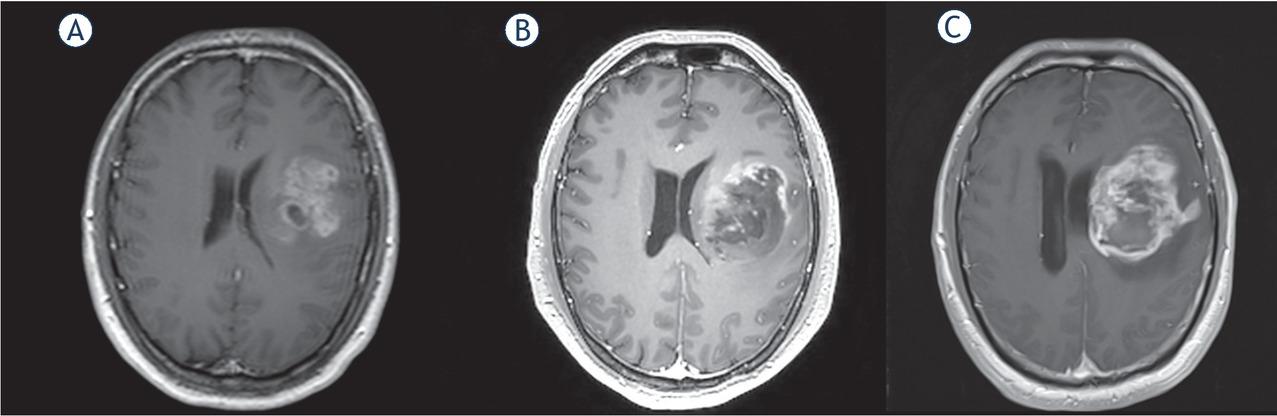

Figure 3

![MRI scans in Patient 4 at 0 (A), 160 (B), 196 (C) and 223 (D) days (fluid attenuated inversion recovery [FLAIR] and T1 with gadolinium sequences).](https://sciendo-parsed.s3.eu-central-1.amazonaws.com/647355e34e662f30ba53aa6c/j_raon-2020-0071_fig_003.jpg?X-Amz-Algorithm=AWS4-HMAC-SHA256&X-Amz-Content-Sha256=UNSIGNED-PAYLOAD&X-Amz-Credential=AKIA6AP2G7AKOUXAVR44%2F20251206%2Feu-central-1%2Fs3%2Faws4_request&X-Amz-Date=20251206T211452Z&X-Amz-Expires=3600&X-Amz-Signature=58b8fca15996e1a2dc4dc49544d9042d94741a640bfdb4774a3ff910664a6f3c&X-Amz-SignedHeaders=host&x-amz-checksum-mode=ENABLED&x-id=GetObject)